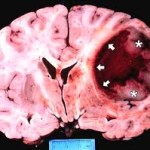

Il team ha sequenziato nove campioni di pazienti affetti da leucemia linfoblastica acuta, di cui quattro con il raro evento traslocazione Robertsoniana . Essi hanno scoperto che per i quattro pazienti con la traslocazione Robertsoniana, il tumore è stato avviato da un evento catastrofico genetico noto come chromothripsis. Questo evento rompe un cromosoma – in questo caso i cromosomi uniti 15 e 21 – e poi li riparazione fondendo i DNA dei cromosomi in un ordine altamente imperfetto e impreciso. Negli altri cinque pazienti, il tumore è stato avviato da due copie del cromosoma 21 in corso di fusione, di solito seguita da chromothripsis.